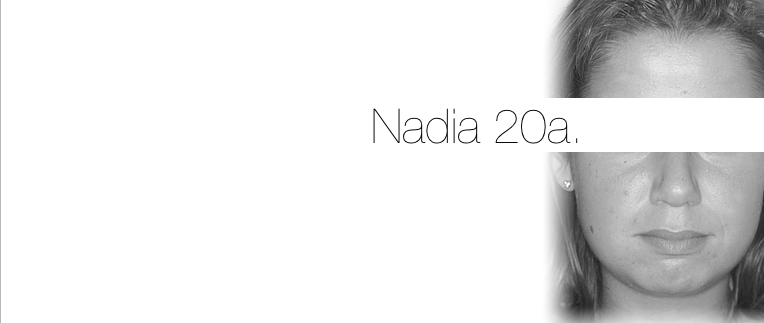

Nome

nadia

Età

20